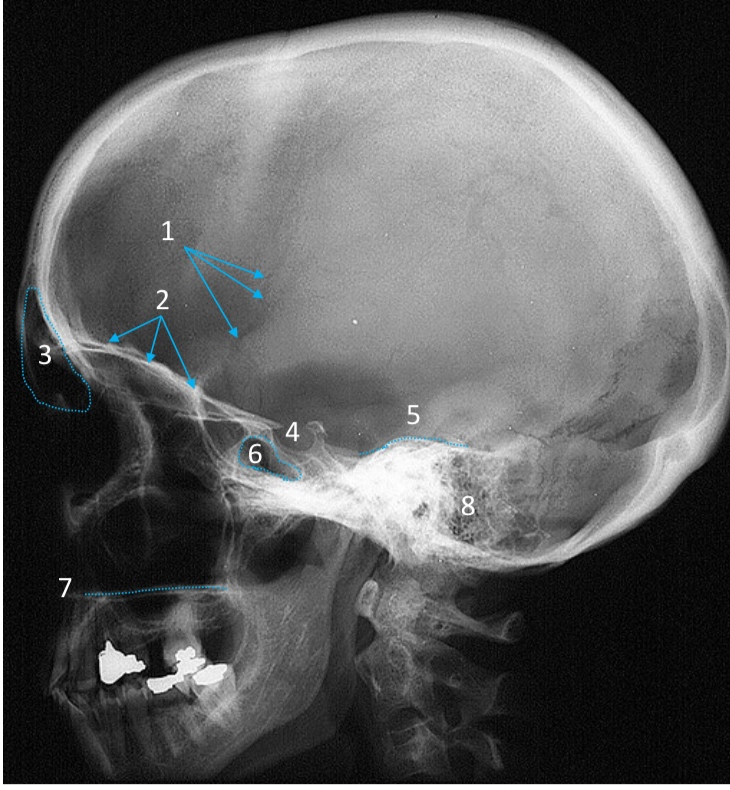

Mandible

ID bone

Maxilla

ID bone

Frontal sinus

ID structure

Pituitary fossa

ID structure

Occipital

ID bone

Lambdoid suture

ID structure

Frontal sinus

ID structure

Orbital margin

Orbit

Maxillary sinus

ID structure

Mandibular condyle

ID structure

Inferior nasal concha

ID structure

Hard palate

ID strucutre

Gonial angle

ID strucutre

Petrous ridge

ID structure

Groove of middle meningeal a.

ID structure

Roof of orbit

ID structure

Frontal sinus

ID structure

Pituitary fossa

ID structure

Petrous ridge

ID structure

Sphenoid sinus

ID structure

Hard palate

ID structure

Mastoid air cells

ID structure

Zygomatic arch

ID structure

Mandibular condyle

ID structure

External auditory meatus

ID structure

Mastoid air cells

ID structure

Foramen magnum

ID structure

Foramen ovale

ID structure

Foramen spinosum

ID structure